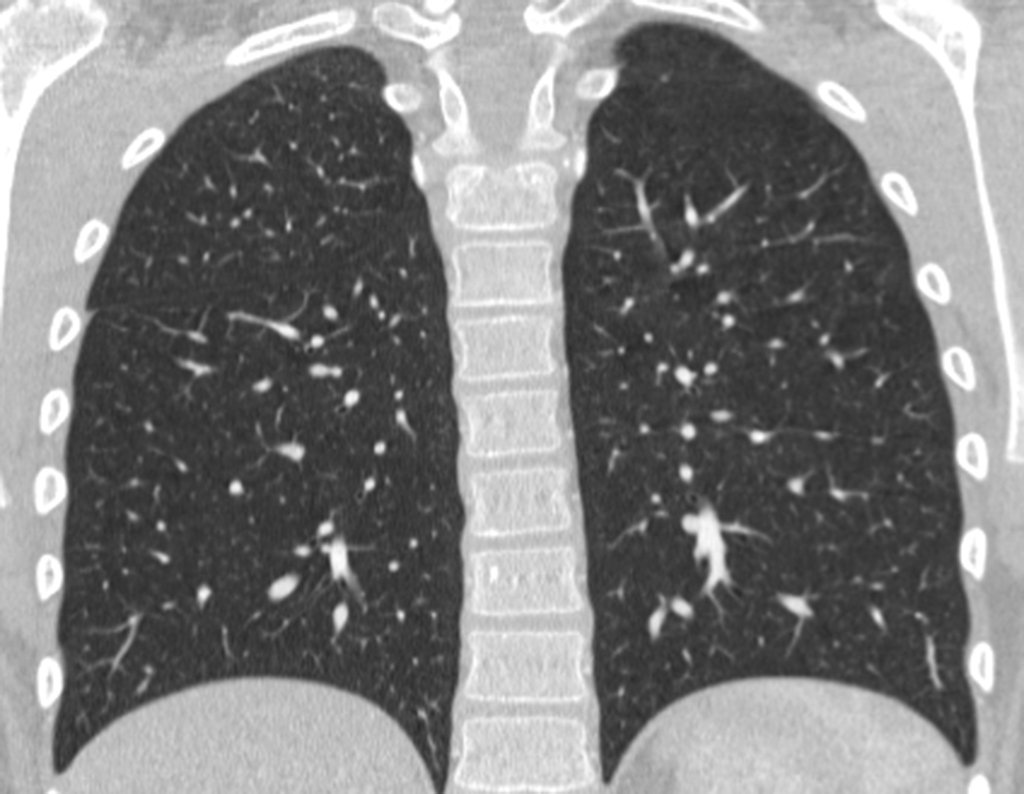

Em 30 de maio de 2016, após seis meses de tratamento com Vimblastina EV, Mercaptopurina e Meticorten (50 mg) o paciente retorna para avaliação. Neste período teve um episódio de dor e edema do punho em Janeiro de 2016, cujas radiografias são apresentadas nas figuras 142 e 143. Manteve o punho imobilizado e reavaliou-se em 11-04-2016, figuras 144 e 145.